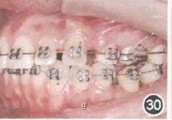

安氏Ⅱ类1分类错合。调整3 6间隙;手术移植45 至36;关闭拔牙间隙,调整移植牙位置,调整咬合关系